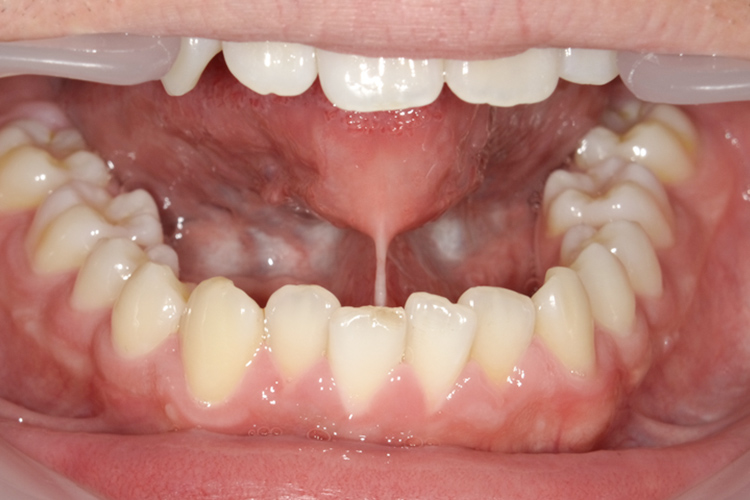

治療前

治療後